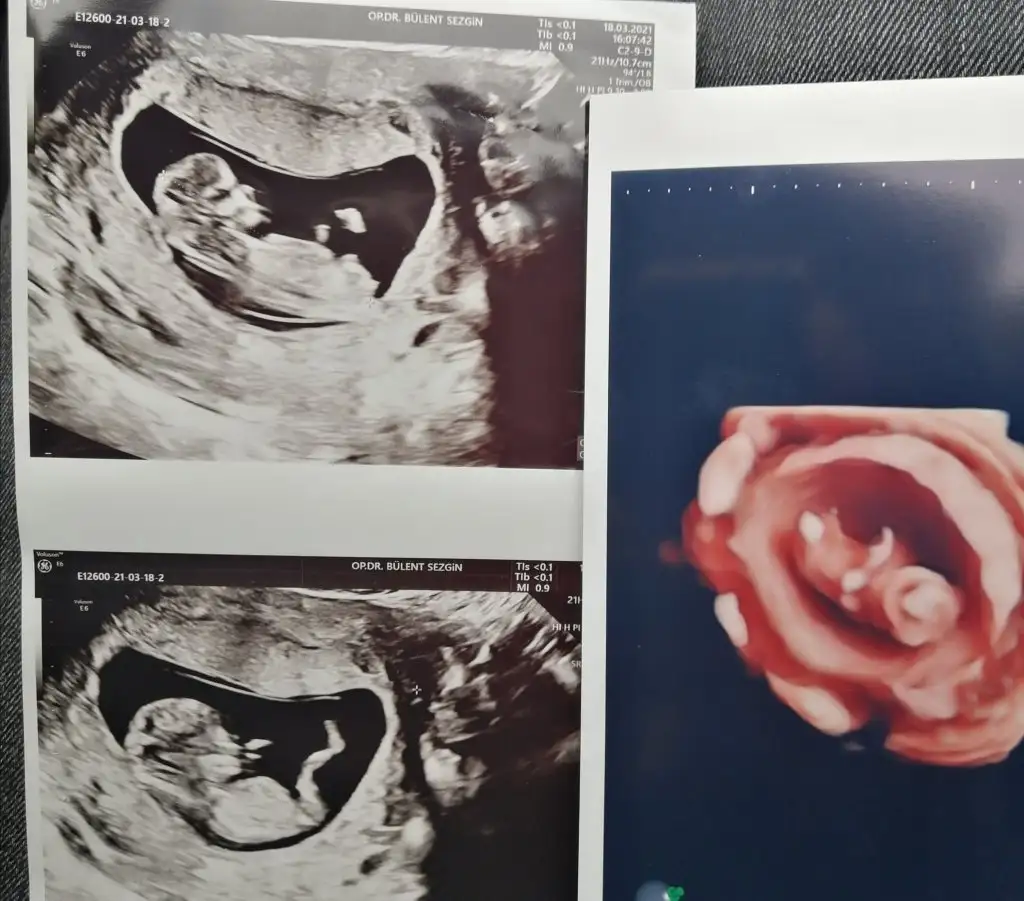

dr soylemeden siz gorun genital nub teorisi ( bebegin cinsiyeti)

Canım 2 hafta önce doktor 11 haftalıkken erkek dedi 13 hafta başka doktora gittim oda bu hafta belli olmz ama aynı senn yöntemle paralel dedi kıza benziyor dedi yani nub yöntemini kullndı kime inannacagımı şaşırdım paraleldi gerçekten 13. Hafta da 11 dede dikti canım hangisi yanılıyor bilmiyorum

Ikra meyra Ikra meyra 13+1 haftalık karından ultrason görüntülerini yorumlayabilir misin?☺️🙏